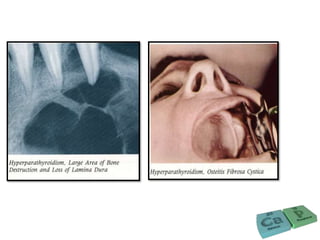

Radiological features

• First radiological sign is subperiosteal resorption of

phalanges of index and middle fingers

• Unilocular or multilocular cystic radiolucencies in bone

• Generalized Attenuation or loss of lamina dura surrounding

the teeth

• Decrease in trabecular density and blurring of normal

trabecular pattern, giving ‘ground glass’ appearance